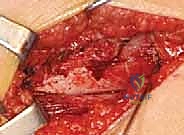

2. الشق الجراحي (The Incision)

يُجري الدكتور هطيف شقاً جراحياً دقيقاً في الجانب الخارجي للفخذ (Lateral Approach). يتميز هذا المدخل بأنه آمن ويحافظ على العضلات الحيوية، وهو ما يعكس خبرة الدكتور في تقنيات الجراحة طفيفة التوغل.

5. قطع العظم (The Osteotomy)

باستخدام منشار جراحي عالي الدقة، يقوم الدكتور هطيف بقطع عظم الفخذ أسفل منطقة المدور الكبير (Subtrochanteric). في هذه المرحلة، يتم إزالة إسفين عظمي صغير (Wedge) بالزاوية المطلوبة لتصحيح التشوه.

6. إدخال الشريحة والتثبيت (Plate Insertion & Fixation)

يتم إدخال نصل الشريحة ذات الزاوية 90 درجة في المسار الذي تم تحضيره في عنق الفخذ. ثم يتم ضم جزئي العظم المقطوعين معاً (إغلاق الفجوة)، مما يؤدي فوراً إلى تغيير زاوية عنق الفخذ إلى الوضع الطبيعي الجديد. يتم تثبيت الجزء الطويل من الشريحة على جسم عظم الفخذ باستخدام براغي قوية من التيتانيوم أو الفولاذ الطبي المقاوم للصدأ.